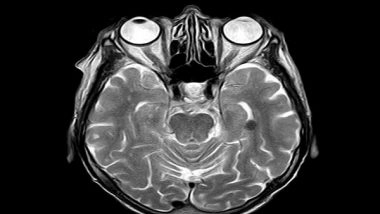

Stockholm [Sweden], December 23 (ANI): Brain age is an MRI-derived estimate of brain tissue loss that has a similar pattern to aging-related atrophy. White matter hyperintensities (WMHs) are neuroimaging markers of small vessel disease and may represent subtle signs of brain compromise.

Brain age was calculated using machine learning on whole-brain tissue estimates from T1-weighted images using the BrainAgeR analysis pipeline in 166 healthy adult participants. WMHs were manually delineated on FLAIR images. WMH load was defined as the cumulative volume of WMHs.